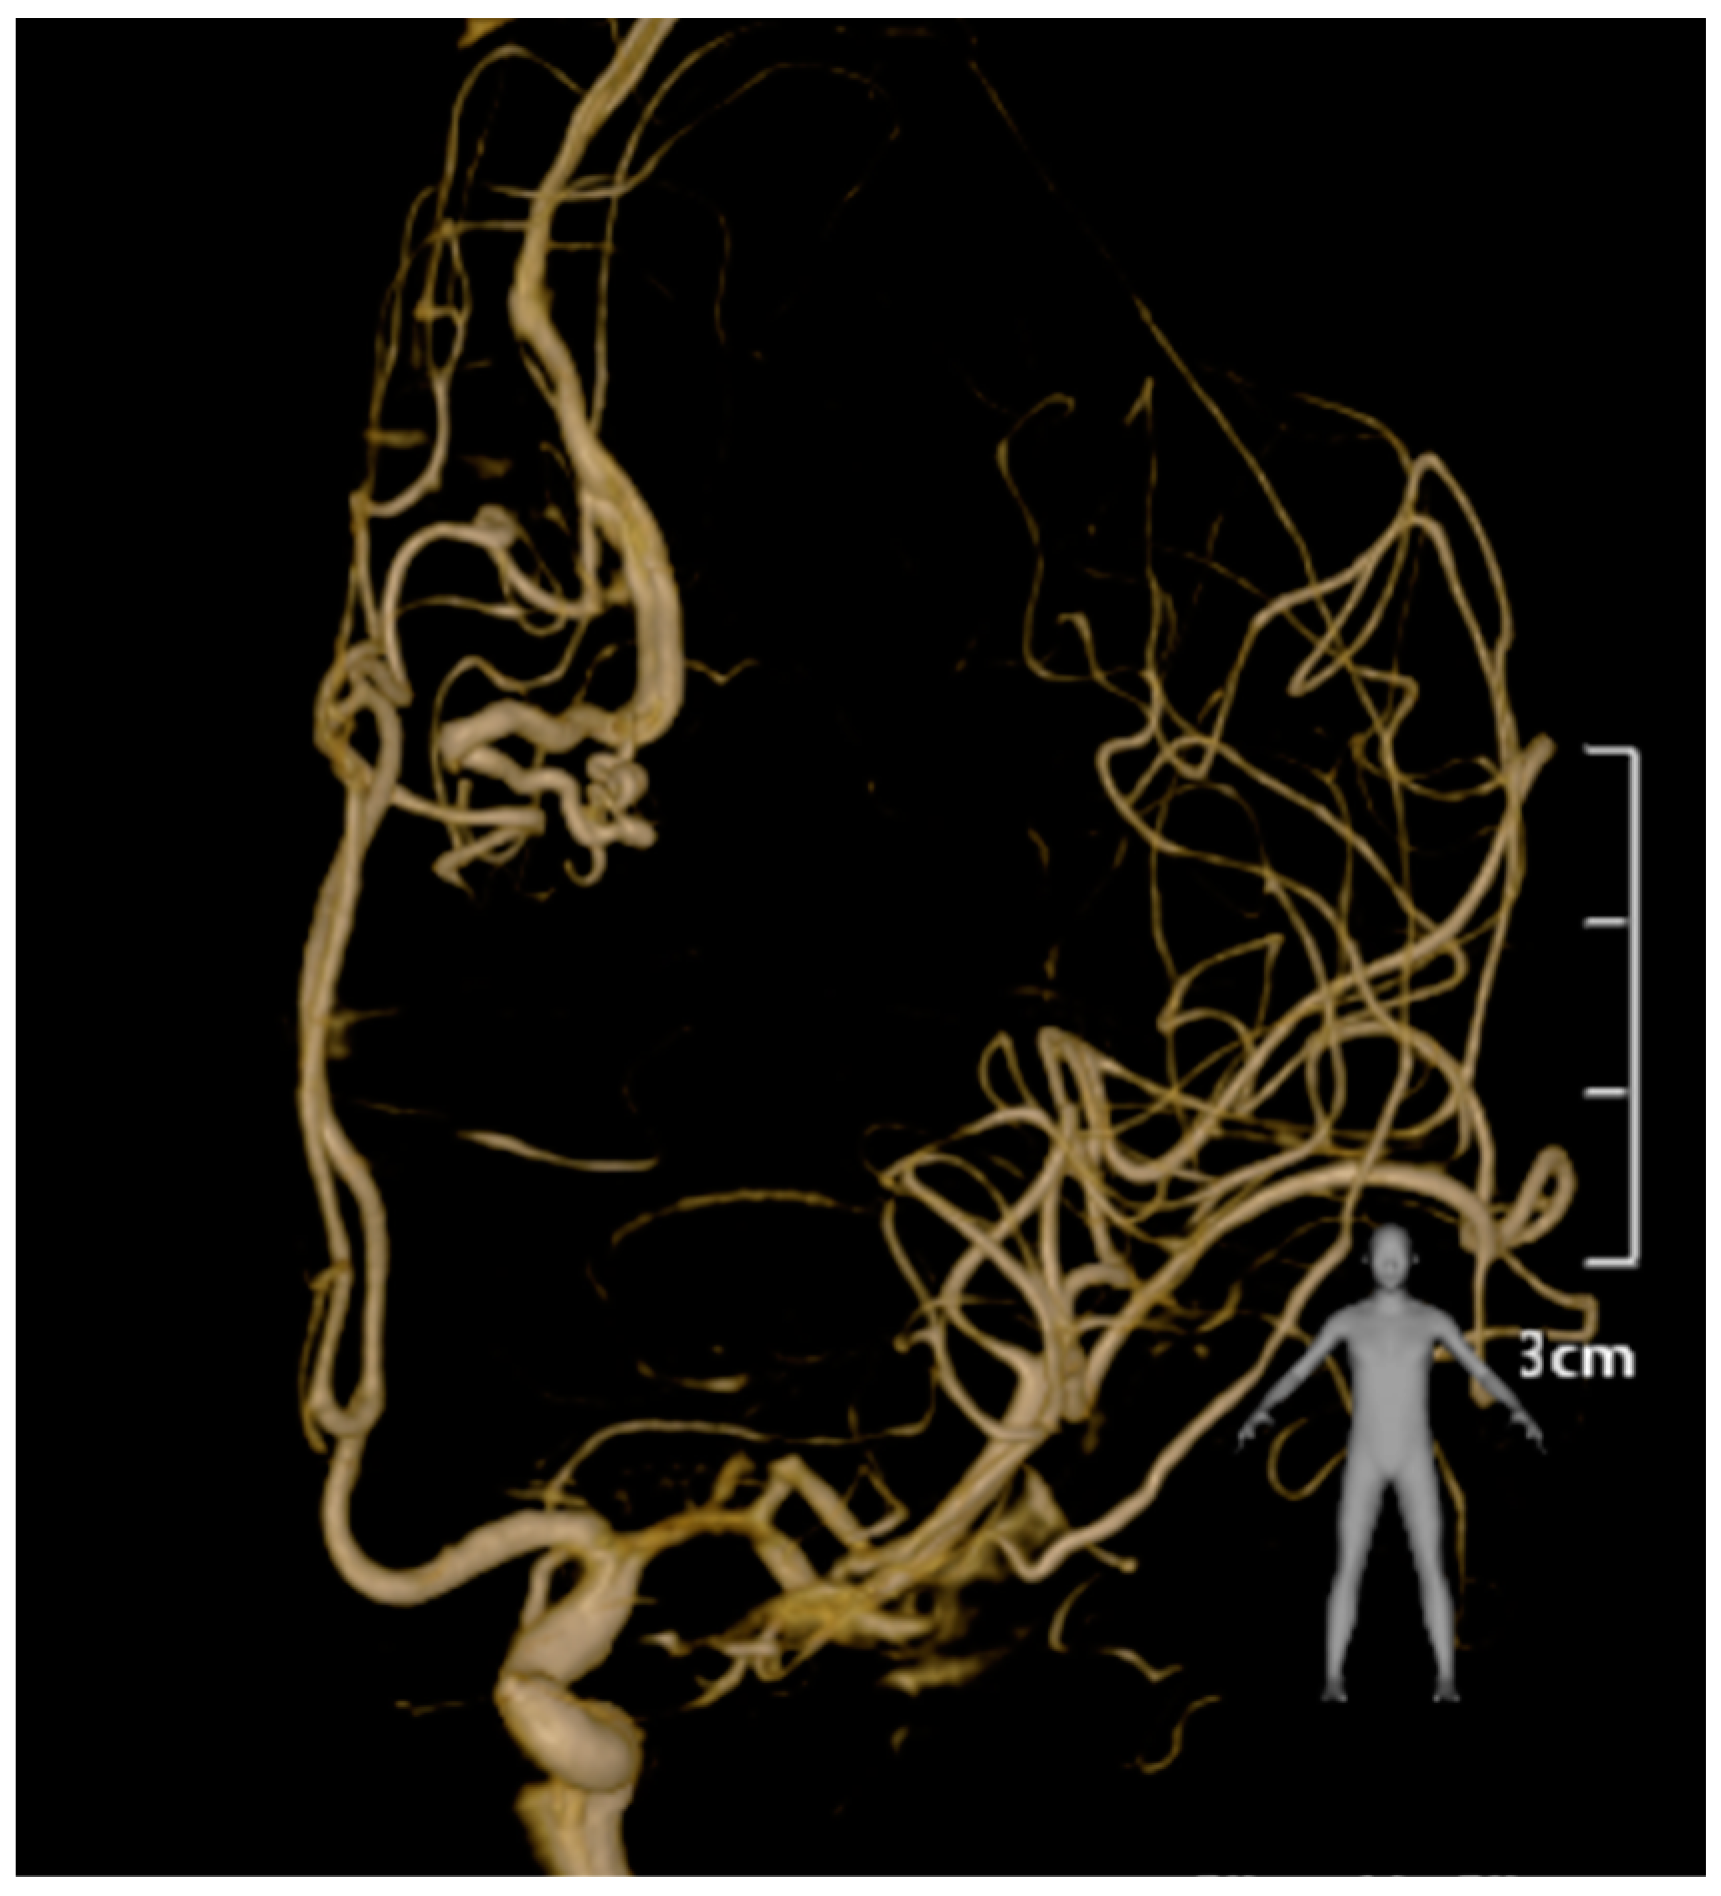

Challenging Management of a Rare Complex Cerebral Arteriovenous Malformation in the Corpus Callosum and Post-Central Gyrus: A Case Study of a 41-Year-Old Female

2. Case Presentation